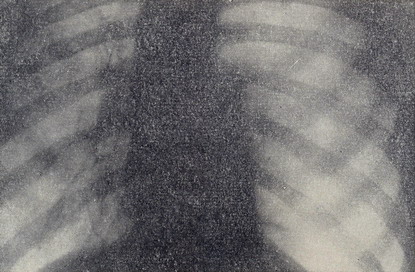

При поступлении состояние средней тяжести, имеется цианоз лица, пальцев рук. Наблюдается небольшая одышка в покое, усиливающаяся при движении. Больной правильного телосложения, пониженного питания - при росте 181 см вес 64 кг. Грудная клетка правильной конфигурации, при дыхании левая половина ее отстает. Число дыханий 22 в 1 минуту. Межреберные промежутки широкие. Перкуторно справа коробочный звук, слева звук с тимпаническим оттенком. Аускультативно справа дыхание прослушивается на всём протяжении лёгкого, жестковатое, слева дыхание не выслушивается. Голосовое дрожание слева отсутствует. Тоны сердца приглушены. Верхушечный толчок определяется у левого края грудины. Пульс 82 в 1 минуту. Артериальное давление 110/80 mm/Hg. Со стороны органов брюшной полости патологии не выявлено. Рентгенологически (рис. 1) левое легкое в состоянии коллапса. Вся левая плевральная полость заполнена газом. Средостение смещено вправо. На ЭКГ синусовая аритмия, вольтаж средний, электрическая ось сердца расположена вертикально. Диагноз: левосторонний спонтанный пневмоторакс.

Рисунок 1 – Прямая рентгенограмма грудной клетки больного А. при поступлении. Левое легкое поджато. Вся левая плевральная полость заполнена газом. Средостение смещено вправо.